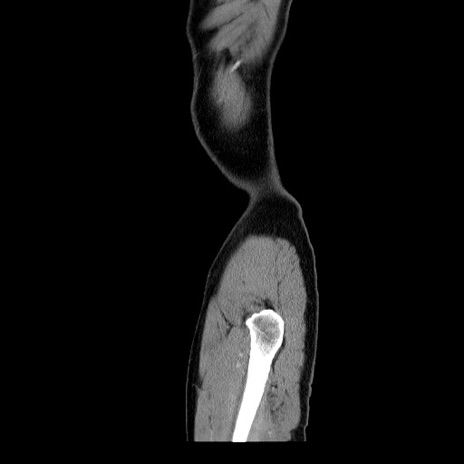

症例34(矢状断像)

【症例】60歳代 男性

【主訴】右鼠径部膨隆

【現病歴】1年程前より右鼠径部膨隆あり。自己にて還納可能だったため放置していた。3時間前より右鼠径部の脱出を認め、還納困難となり受診。

【身体所見】右鼠径部に小児頭大の膨隆あり。弾性硬であり、用手還納は困難。左鼠径部にも膨隆を認める。脱出はなし。